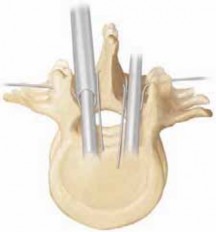

22. The unit rod incorporates these concepts into one instrumentation system2,4,10,13 (

FIG 3A,B

).

23. The unit rod has a prebent sagittal contour and comes in sizes of 250 mm to 450 mm. Both quarter-inch and 3/16-inch-diameter rods are available. The quarter-inch rod should be used whenever possible, reserving the 3/16-inch rod for patients with a very thin gracile pelvis.

24. Some surgeons are using pedicle screws for segmental fixation, especially if there is a severe rotational component to the curvature. Caution should be taken when the bone is severely osteopenic, as the pedicle screws may pull out of the bone.

A

B

FIG 3 • A. The unit rod is available commercially in a range of sizes. B. Drill guides are provided for placement of the pelvic limbs as well as the impactor and pusher for the rod.

CDE

---

F

### FIG 3 •

(continued)

C–E. Cantilever effect of the rod correcting pelvic obliquity and scoliosis. The rod is gradually pushed to each vertebra and each wire is tightened, gradually correcting the deformity using transverse forces. F. Anterior release: wedge resections of the discs are performed around the apical vertebrae if the spinal deformity is stiff.

1. The unit rod is especially powerful as a cantilever to correct pelvic obliquity (

FIG 3C–E

2. Anterior release for scoliosis is required for larger stiff curves that do not bend out on the bending test (generally greater than 90 degrees) (

FIG 3F

1. Anterior release is also recommended for severe hyperlor-dotic and hyperkyphotic spinal deformities.8